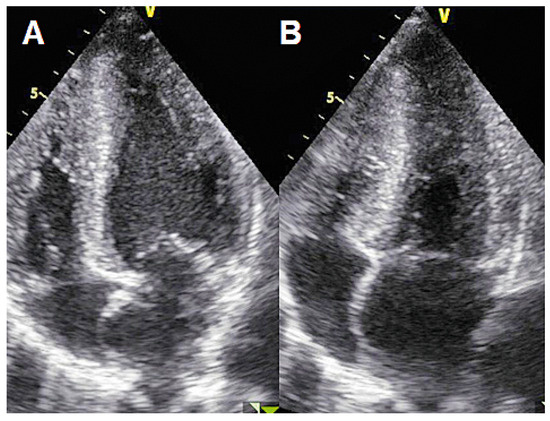

Case 2

Case 3